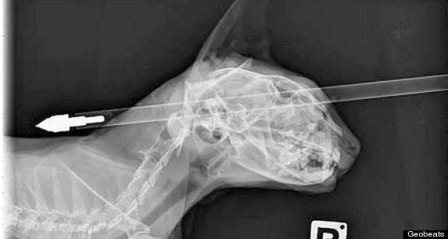

(Dân trí) - Một con mèo ở Wainuiomata, New Zealand đã sống sót một cách kỳ diệu sau khi bị mũi tên dài bắn xuyên qua đầu từ mặt ra sau gáy.

Chú mèo Moo Moo bị mũi tên bắn xuyên qua đầu.

Mặc dù bị bắn xuyên qua đầu nhưng may mắn không ảnh hưởng đến tính mạng.